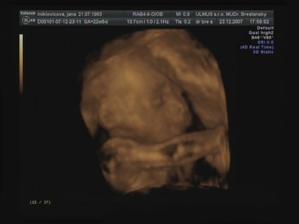

Emuška

Ahojte už som tu z 1,5cm som vyrástla na takúto krásnu slečnu moje meno je Emka a narodila som sa 4.4.2008 o 12:25 hod v Topolčianskej nemocnici vážila som 3510g a najviac na svete ma ľúbia maminka a ocinko